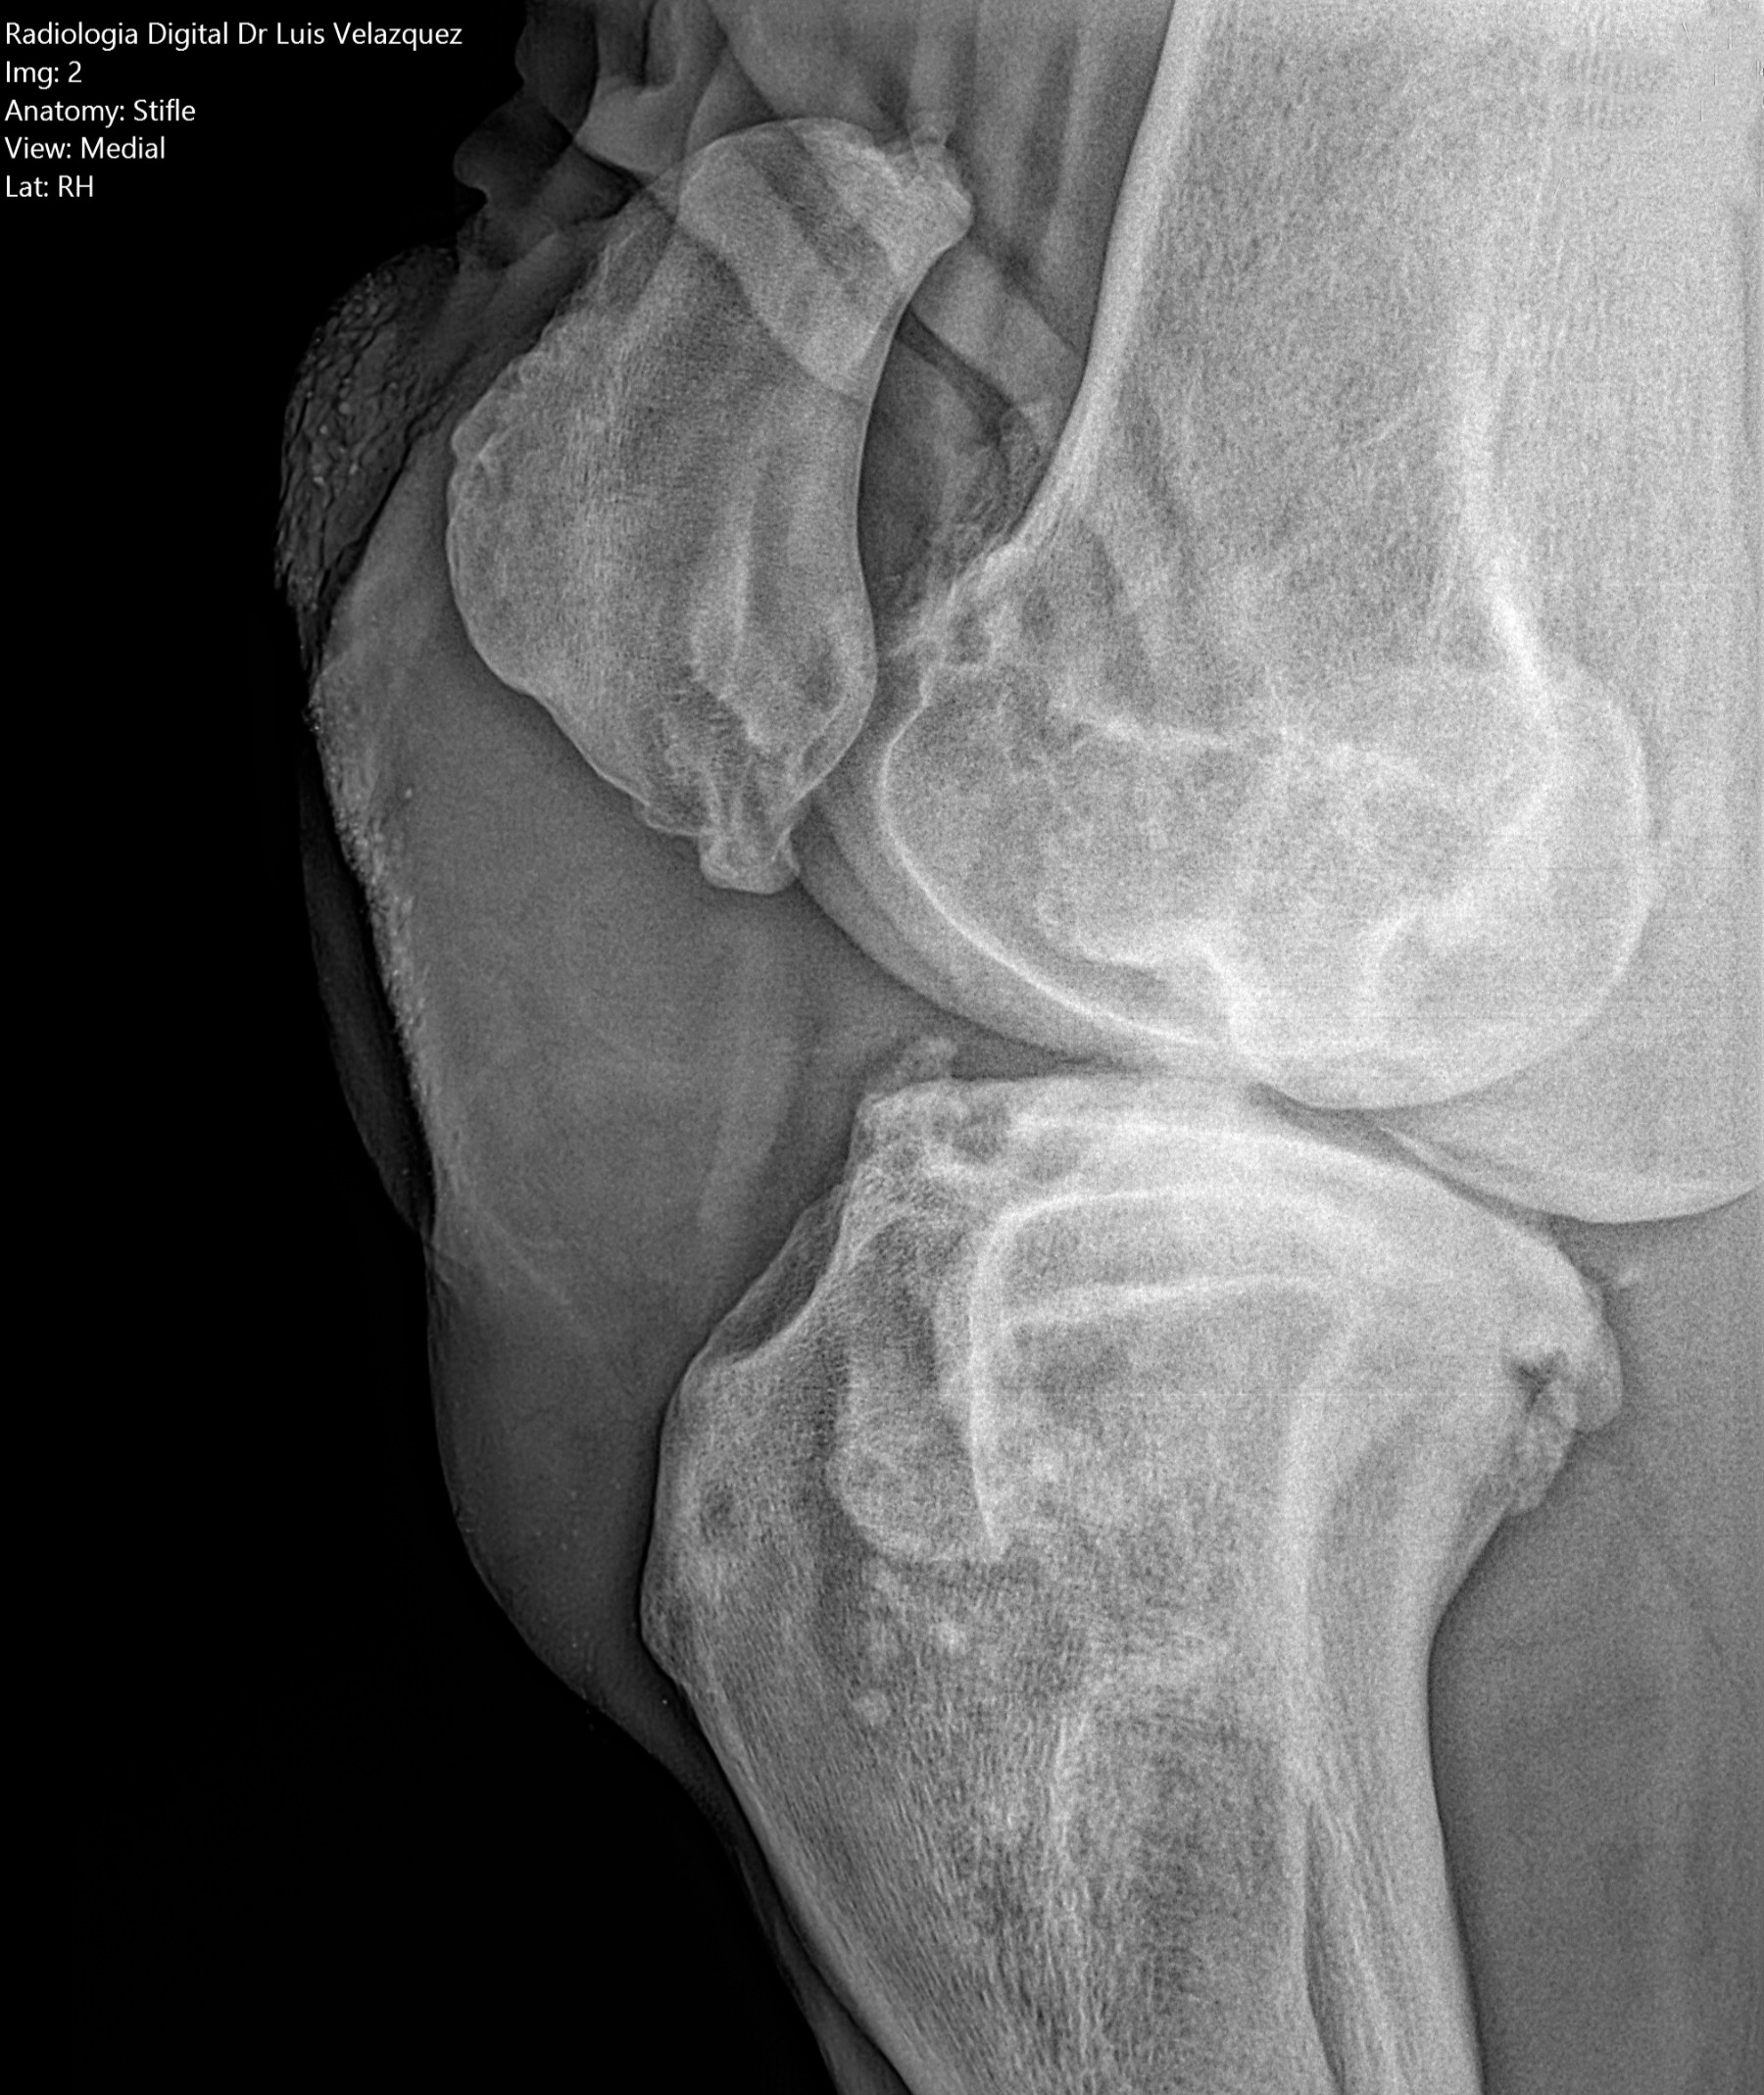

Radiología Digital como Herramienta Complementaria en el Dictamen de Bienes Muebles

Los caballos de salto, en competencia, pueden derribar obstáculos y lastimarse. Si se golpean, no siempre claudican. Considerando al calor como un signo de inflamación, se evaluaron los cambios térmicos de 6 áreas de las extremidades torácicas y pelvianas de 23 caballos de salto en nivel de competencia de 1.05 a 1.60 m de altura, por medio de termografía durante 4 días de competencia (N=2208 áreas).